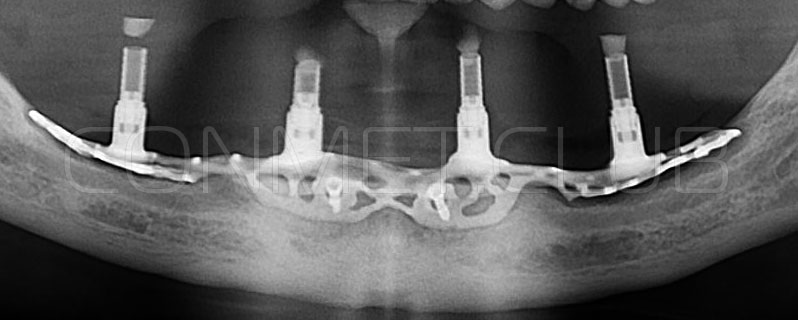

2. После этого произвели компьютерное моделирование самого имплантата и фиксирующих элементов. Примечательно, что в абатментах, использовался отлично зарекомендовавший себя и проверенный десятилетиями интерфейс КОНМЕТ! В результате получили несколько специальных файлов, позволяющих не только сделать сам имлантат, но еще до операции изготовить и сами зубы. Данные файлы передали в изготовление на специальном 3D оборудовании.

Имплантат напечатали из особого, биосовместимого, медицинского титана на предприятии имеющим соответствующую медицинскую лицензию. Толщина имплантата составила 0,8 мм, а вес всего несколько грамм!

Первый вывод к которому мы пришли, это то, что для данных конструкций имплантатов сохранять внутренний интерфейс с шестигранником и конусом Морзе нецелесообразно из-за ограничения возможностей современной 3D печати титана. Кроме того, техническая обработка после 3D печати такого интерфейса представляет значительные трудности и ведет к неоправданному увеличению цены. Поэтому пришли к единодушному мнению, что лучший вариант-это опорные элементы полностью повторяющие абатменты-мультиюниты.

Клинические работы с субпериостальными имплантатами производства Конмет, проведенные в 2019 году, позволили унифицировать интерфейс данных имплантатов под современный цифровой протокол. Более того, необходимые конструкционные элементы были введены в официальную базу под программу Exocad. Что позволило сократить время изготовления зубного протеза до 1-3 дней!